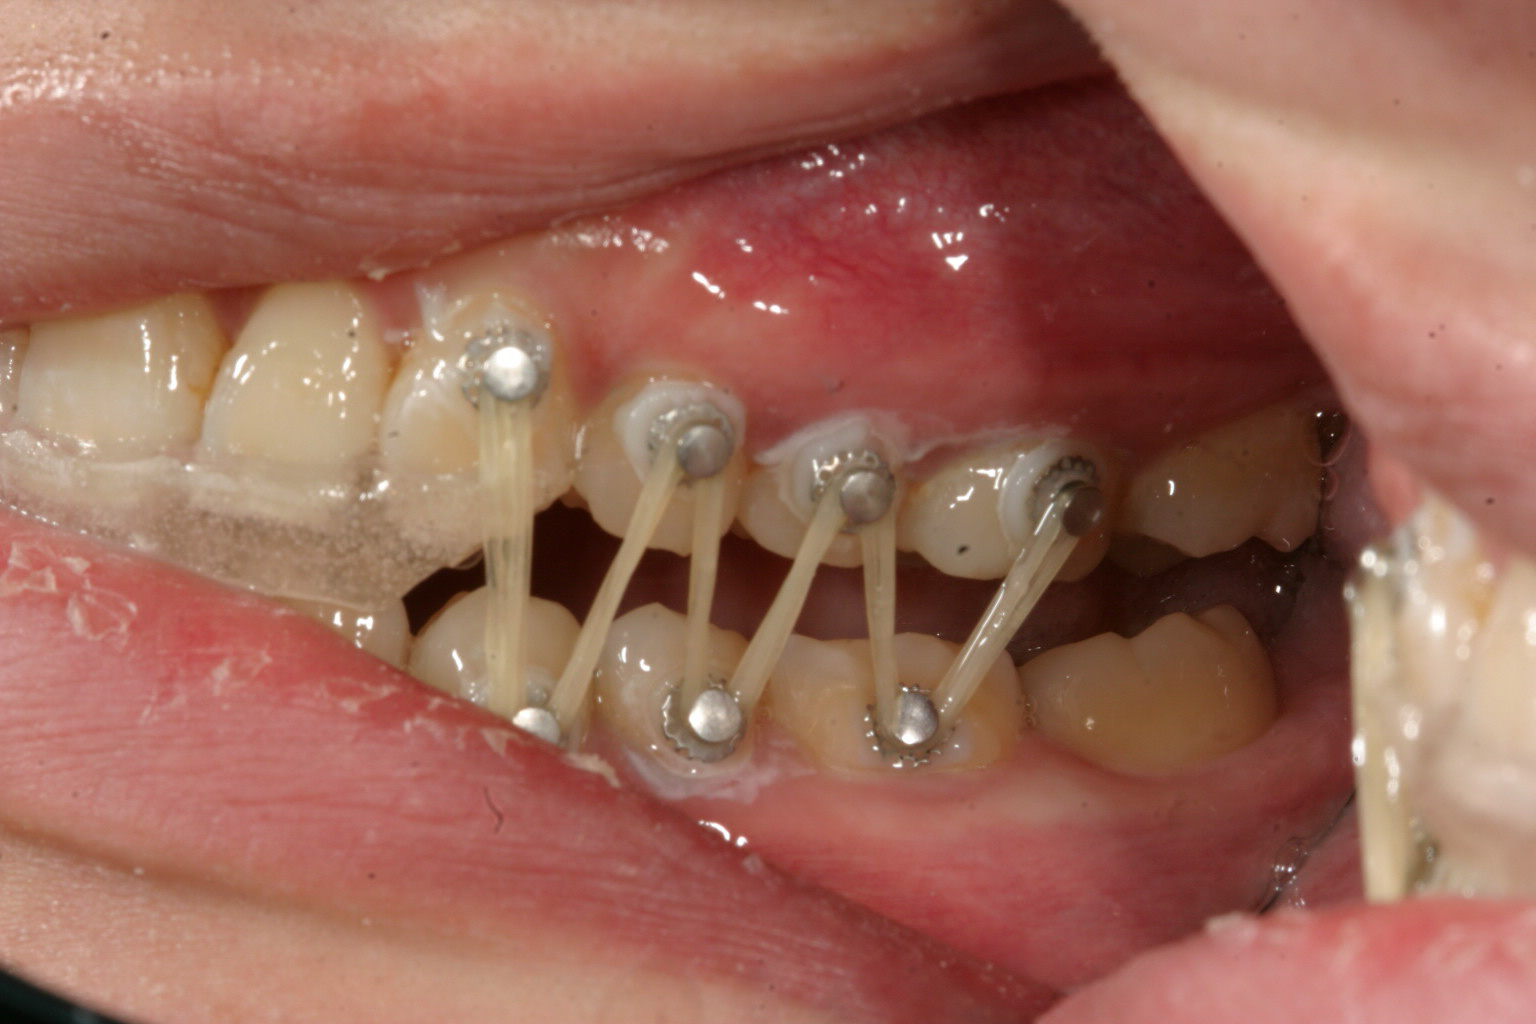

前歯部に自家製のジグ咬ませて右側にアップダウンエラスティックを使用してます。